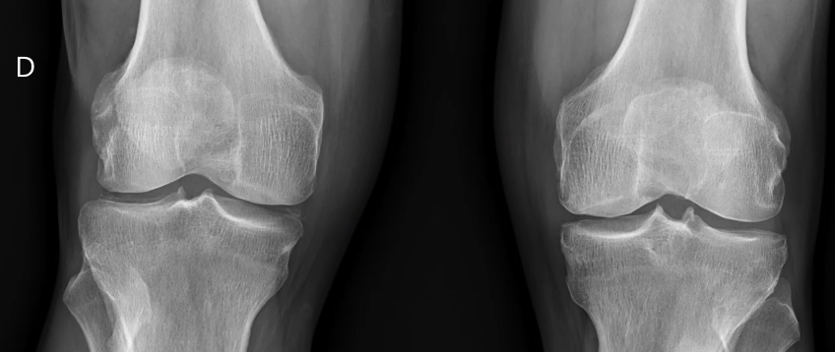

Radiografía: línea radiolucente paralela a la superficie tibial externa y en región meniscal medial. Sugestivo de condrocalcinosis.

Orientación diagnóstica. Por ecografía Patología meniscal (Condrocalcinosis) + por la exploración física Artrosis.